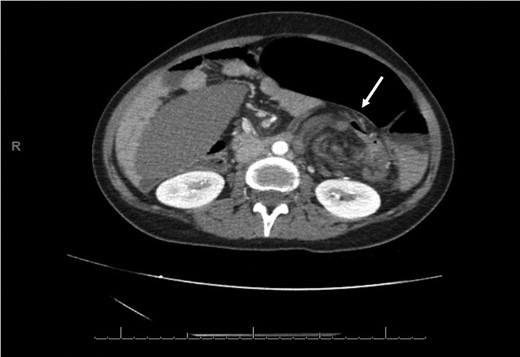

An axial CT shows dilated engorged mesenteric vessels (white arrow) indicating mesenteric varices.

Laboratory investigation showed a white blood cell count of 15.13 × 103/UL, (mainly neutrophilia of 90.3%), a hemoglobin level of 9.4 g/dL, and a platelet count of 189 × 103/UL. The other biochemical parameters including liver enzymes were normal apart from a trace of jaundice, with total Bilirubin of 2.43 mg/dL and direct Bilirubin of 0.45 mg/dL. Chest X-ray showed bowel loops at the splenic fossa (Fig. 1). An initial diagnosis of a torted ovarian cyst was made. A pelvi-abdominal ultrasound revealed normal adnexa but a right-sided soft pelvic-abdominal mass with the absence of a splenic shadow at the left hypochondrium. Subsequently, CT scan of the abdomen and pelvis revealed a large right-sided infarcted spleen of 30 × 16 × 10 cm3 (Fig. 2) and a ‘whirl sign’ of the splenic pedicle (Fig. 3). Furthermore, CT scan showed signs of portal hypertension (Fig. 4) associated with mesenteric varices (Fig. 5). The patient subsequently underwent a surgical exploration.

A wandering spleen can be complicated by hypersplenism, splenic infarction, portal hypertension and/or varices. Although a few cases of a wandering spleen complicated by the fundal varices and left sided portal (sinistrial) hypertension have been reported, but complications of mesenteric varices are considered rare [7]. To the best of our knowledge, this is the third reported case after two cases reported by Zarroug et al. [8] of a wandering spleen complicated by the mesenteric varices; both were managed successfully by splenectomy.

The authors concluded that, in this case the most likely mechanism of portal hypertension with mesenteric varices in absence of portal vein thrombosis is the mechanical occlusion of extrahepatic portal vein at the level of superior mesenteric and splenic vein confluence due to splenic torsion and its migration to the right side of the abdomen. Subsequently, this led to retrograde long-standing vascular congestion, splenic vein occlusion, and eventually its infarction along with portal hypertension and mesenteric varices.